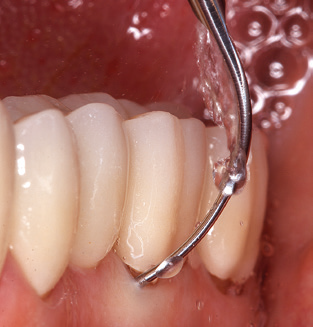

L'aggiornamento della storia medica del paziente è un aspetto importante di SPT e dovrebbe avvenire almeno una volta all'anno. Aiuta il team dentale a identificare e documentare eventuali nuovi fattori di rischio. Soprattutto quando un paziente viene curato per molti anni, è importante stabilire se i fattori di rischio per la salute specifici del paziente e generali sono cambiati. Ciò riguarda principalmente un aumento del rischio a causa del diabete, ma altre condizioni generali (malattie cardiovascolari e neoplasia) possono anche produrre un profilo di rischio modificato a seguito del trattamento eseguito e della somministrazione dei farmaci. Di conseguenza, l'aggiornamento della storia medica come parte di SPT è molto importante, poiché un profilo di rischio modificato può innescare la necessità di adattare l'intervallo di trattamento. Nel passaggio successivo, è importante prestare la dovuta attenzione alla diagnostica. Mentre gli strumenti sono un aspetto centrale di SPT, i risultati e la loro documentazione non devono mai essere trascurati. I risultati parodontologici sono essenziali per una buona diagnosi; aumenti della profondità della tasca e l'indice BOP sono chiari indicatori dell'avanzamento della malattia parodontale e perimplantare. Pertanto, il team non dovrebbe evitare di sondare anche gli impianti, con l'obiettivo di raccogliere i dati richiesti. Allo stesso tempo, è importante utilizzare sonde parodontali con segni millimetrici. Le sonde metalliche sono già state utilizzate per determinare la profondità della tasca attorno ai denti naturali per decenni. Nel caso degli impianti, la sfida di registrare profondità delle tasche corrette e riproducibili è ancora maggiore. Poiché la discrepanza tra il diametro dell'impianto e il contorno della sovrastruttura si traduce regolarmente in un over-contouring della sovrastruttura, le sonde flessibili che presentano ancora marcature millimetriche sono una soluzione sensata per misurare la profondità della tasca attorno agli impianti (ad es. Colorvue Kit PCV11KIT6, HuFriedy; Fig. 4 ).

Fig. 4: Sonde flessibili con marcature millimetriche sono consigliate per il sondaggio di impianti dentali (ad es. Colorvue Kit PCV11KIT6, HuFriedy). - Fig. 5a e b: Un inserto diritto (1P, W&H Dentalwerk Bürmoos GmbH) è uno strumento adatto per l'uso su tutti i denti naturali. - Fig. 6: Inserti curvi (3Pr / 3Pl, W&H Dentalwerk Bürmoos GmbH) si prestano alla lavorazione di aree difficili da raggiungere del dente e delle superfici radicolari (ad es. Forcazioni). - Fig. 7: L'inserto esagonale conico per la pulizia dell'impianto (1I, W&H Dentalwerk Bürmoos GmbH) consente una pulizia atraumatica ed efficace della superficie della corona e del moncone. - Fig. 8: Le curette in titanio e carbonio sono strumenti adatti per la pulizia manuale delle superfici dell'impianto.